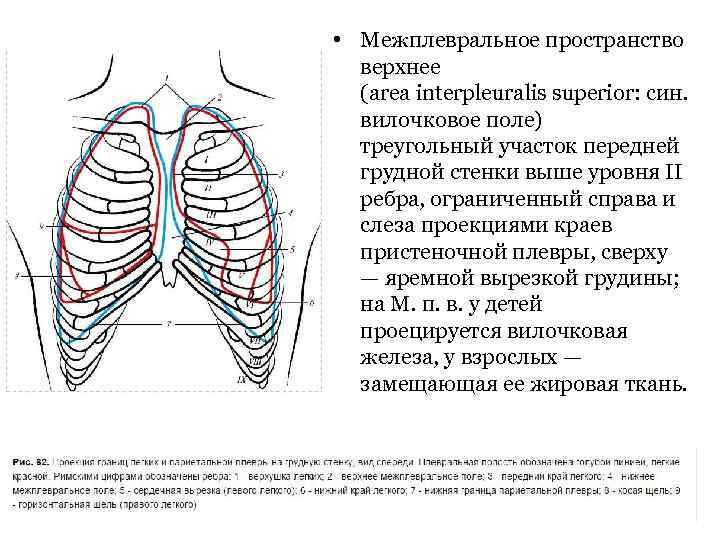

• Межплевральное пространство верхнее (area interpleuralis superior: син. вилочковое поле) треугольный участок передней грудной стенки выше уровня II ребра, ограниченный справа и слеза проекциями краев пристеночной плевры, сверху — яремной вырезкой грудины; на М. п. в. у детей проецируется вилочковая железа, у взрослых — замещающая ее жировая ткань.

• Межплевральное пространство верхнее (area interpleuralis superior: син. вилочковое поле) треугольный участок передней грудной стенки выше уровня II ребра, ограниченный справа и слеза проекциями краев пристеночной плевры, сверху — яремной вырезкой грудины; на М. п. в. у детей проецируется вилочковая железа, у взрослых — замещающая ее жировая ткань.